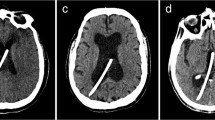

A total of 10 catheter implantations were performed in human cadaver specimens. All catheters were implanted in the frontal horns of lateral ventricles in the first attempt leading to a 100% first pass success rate. The 3D Euclidean error (3D distance) between the software-planned and the frame-targeted coordinates was 1.8 ± 0.6 mm (n = 10, Fig. 3J). We also measured the deviation of the catheter from its trajectory in the XY plane of the target and referred to it as the trajectory error. The trajectory error was found to be 1.9 ± 0.8 mm (n = 10, Fig. 3J). The distance of the margin of catheter tip from the FOM was found to be 3.9 ± 1.6 mm (n = 10). The average time taken for key placement, surgical planning (including fiducial registration), and EVD implantation was 1.6 ± 0.4 min (n = 4), 9.4 ± 3.5 min (n = 10), and 14.7 ± 2.6 min (n = 8) min, respectively (Fig. 3K). Two observations for implantation time were excluded as they employed a pre-existing burr hole. The total time for the procedure excluding the CT scan was 26.5 ± 3.1 min per implant (n = 8, Fig. 3K). Figure 4 shows the targeting accuracy assessment of a representative experiment by superimposing the planned trajectory on the actual trajectory using COMPASS surgical planning software (COMPASS International Innovations, Rochester, MN). The entire procedure was completed on the CT scanner table without transporting the specimen.

Surgical workflow (A–H) and results (I–K) from cadaveric pre-clinical study. (A) Specimen positioning for EVD catheter implantation. (B) The EVD key and localizer were mounted on the specimen and (C) a pre-procedure CT scan was obtained. (D) The CT data was transferred to surgical planning software and fiducial registration was performed. Stereotactic coordinates were obtained for a target close to the foramen of Monro and an appropriate trajectory (collar and arc angles) was chosen. (E) The stereotactic coordinates, and the arc and collar values obtained in the previous step were dialed into the stereotactic targeting device and the device was mounted on the EVD key. (F) A probe was used to mark the site of incision along the trajectory. (G) An incision was made at the marked site and a 5 mm burr hole was stereotactically drilled into the bone with the help of a drill guide and a standard #9 drill bit. (H) A metal catheter was then implanted into the brain and secured in place. A post-procedure CT scan and target verification was performed thereafter (not shown). (I) A schematic explaining the 3D Euclidean error and trajectory error. (J) The 3D Euclidean error and targeting error were found to be 1.8 ± 0.6 mm (n = 10) and 1.9 ± 0.8 mm (n = 10) (K) Stepwise and total procedure time: key placement (1.6 ± 0.4 min, n = 4), surgical planning (9.4 ± 3.5 min, n = 10), EVD catheter implantation (14.7 ± 2.6 min, n = 8) were completed in total 26.5 ± 3.1 min (n = 8).

CT images showing robust targeting accuracy in a representative pre-clinical experiment (COMPASS software). The actual location of catheter tip (red circle) is seen to be overlying the planned location (blue dot). The bottom right panel shows the actual catheter trajectory (white glow) with superimposed planned trajectory (red line). Cerebral vasculature was avoided while placing the catheter.

The catheter tip was located within ipsilateral frontal horn in all implantations and thus judged Grade I (optimal/adequate) as per Kakarla et al.'s clinical grading system1 (supplementary Table S1). For 9 implantations, the catheter tip was located within 5 mm of ipsilateral FOM and judged as ideal based on Fargen et al.’s4 grading system (supplementary Table S2). For one implantation, the tip was placed 8 mm from the FOM in the ipsilateral lateral ventricle and judged as acceptable. For experiments emulating surgical planning with CTA, a thorough visual inspection of the post-procedure CT images revealed no direct contact of the catheter with visible vessels (n = 5, see Fig. 4, bottom right panel for representative image).

The EVD key and localizer were secured on the back half of the cadaver head with two midline pins and two side screws (Figs. 3B, 1C). The anterior pin was placed 17–18 cm behind the nasion in the midline. The specimen was imaged in a CT scanner with a slice thickness of 0.6 mm (Fig. 3C). The images were transferred to a surgical planning computer. COMPASS software was used for fiducial registration and surgical planning. A target in the frontal horn of lateral ventricles (Fig. 3D) and a trajectory which avoids the eloquent cortex as well as CT visible vasculature were chosen. The software provided the coordinates for the target, X, Y and Z value, as well as the trajectory, arc and collar angles.

The X, Z, arc, and collar values of the surgical target were dialed into the stereotactic device (Fig. 3E) and it was locked on the EVD key at the designated Y coordinate. The site for incision was marked (Fig. 3F) followed by scalp incision and stereotactic drilling of a 5 mm diameter burr hole (Fig. 3G). The dura was punctured with a sharp needle. A metal catheter was then advanced to the target and secured in place (Fig. 3H). A post-procedure CT scan was performed to verify the catheter coordinates and trajectory using COMPASS. To account for errors involved in the frame placement and registration and in having different head shapes, all surgical steps right from the EVD key and localizer placement to the post procedure CT scans were repeated multiple times and on multiple cadaver heads. All steps were performed by a post-doctoral fellow who completed medical school training and has prior experience in cadaveric stereotactic procedures.

The first attempt success rate, targeting error (3D Euclidean error), trajectory error, catheter tip location from FOM, number of blood vessels in contact with the catheter (radiographic assessment), and surgical time were assessed and documented. The location of catheter tip on the post-procedure CT scan was evaluated as per the clinical grading systems given by Kakarla et al.1 and Fargen et al.4.